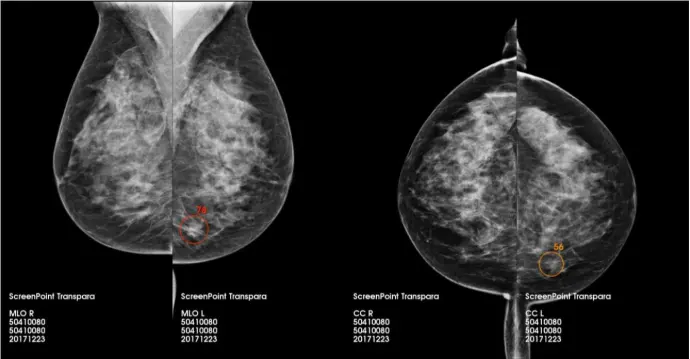

Transpara®, desarrollado por ScreenPoint Medical, es una solución avanzada de inteligencia artificial diseñada para apoyar a los radiólogos en la lectura de mamografías tanto 2D como 3D. Aprobado por la FDA y con marcado CE, está presente en más de 30 países y ha procesado más de 7 millones de mamografías.

Transpara lleva a cabo un análisis exhaustivo de cada mamografía, asignando una puntuación de riesgo tanto a nivel global como por regiones específicas de la imagen, lo que permite una priorización efectiva de los casos sospechosos. Esta funcionalidad no solo mejora la precisión diagnóstica, sino que también reduce la incidencia de falsos positivos y optimiza considerablemente el tiempo de interpretación por parte del profesional de la salud.